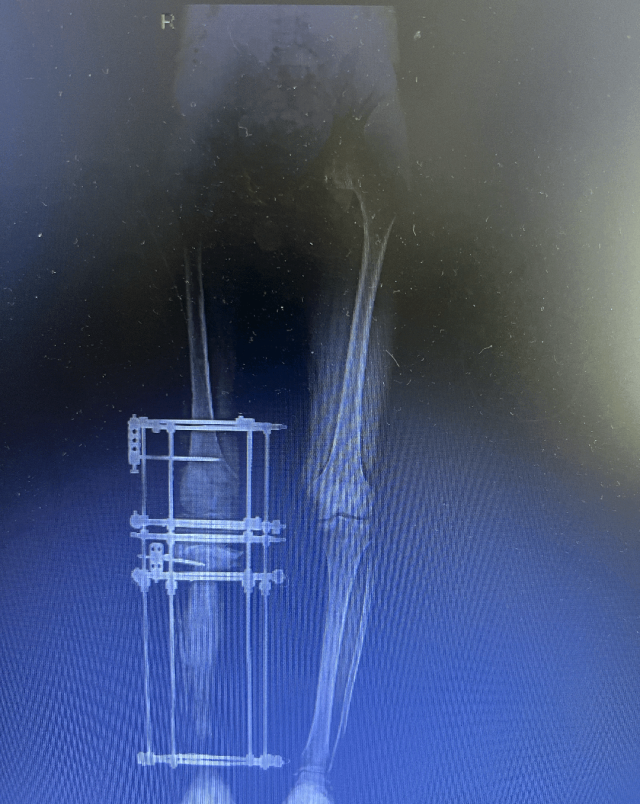

2024年为了保住小飞的腿

团队决定拼一把

先给小飞做了全面检查

又专门设计了手术方案

之后,团队给小飞做了两次关键手术

先清理干净伤口里的感染和坏死的骨头

再用 “骨搬移” 的方法

让剩下的好骨头慢慢长

惊喜的是

小飞的骨头真的在一点点长

每天长 1 毫米

最后竟把 20 厘米的骨头缺口全补上了!

现在小飞终于能笑着说

我现在可以一口气走 20 分钟了!